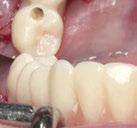

Ejecución técnica protésica

Dado que la estabilidad primaria se ha conseguido en la mayoría de los implantes, coincidiendo con la previsión propuesta en la planificación, procedemos ahora a la fase protésica. En el caso que nos ocupa, la paciente reside lejos, por lo tanto, colocamos tapones sobre los pilares transepiteliales y descansa en la sala de recuperación (Figura 30).

El procedimiento de diseño, impresión, pulido y cementación de aditamentos consume

Figura 34. Rehabilitación superior impresa en resina Bego VarseoSmile TriniQ® lista para atornillar. Se han anulado de la oclusión aquellos implantes que no obtuvieron una estabilidad primaria superior a 35 N/cm2 Figura 31. Escaneado intraoral postcirugía. Figura 32. Rehabilitación recién impresa a través de impresora Varseo XS con resina Bego VarseoSmile TriniQ®. Figura 33. Ajuste pasivo entre aditamentos protésicos y la rehabilitación impresa.

36 CIENCIA Y CLÍNICA. Caso clínico Gaceta Dental · N o 366 | Mayo 2024

aproximadamente una hora y media. Usamos resina Bego VarseoSmile TriniQ® para puentes definitivos. Aunque en este caso la vamos a usar para confeccionar unas prótesis fijas atornilladas provisionales de larga duración, dado al aumento de dimensión vertical que vamos a realizar a la paciente, de esta forma obtendremos una neuroprogramación de la ATM reinstaurando una Dimensión Vertical apropiada y mejorando la estética facial de la paciente. Excluimos de la carga aquellos implantes que no obtuvieron una estabilidad primaria superior a 35 N/ cm2. El material permite la realización de una carga inmediata en material definitivo en puentes (Figuras 31 a 38).